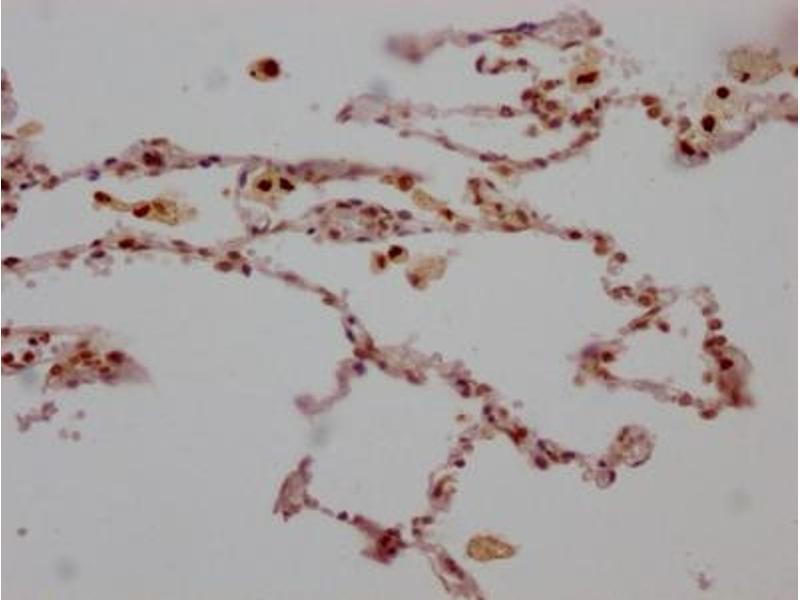

- IHC:1:50-1:200